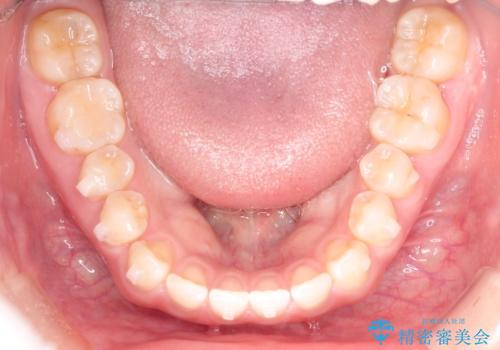

前歯の隙間を閉じたい インビザラインによる矯正

- 上下の前歯に隙間があるとのことで来院されました。

インビザラインにて隙間を閉じる矯正を行いました。